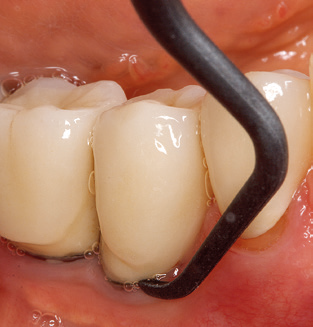

Following machine cleaning of the tooth and implant surfaces, the surfaces of the natural teeth are cleaned manually using standard hand instruments. When performing manual cleaning, particular attention must be given to maintaining the correct angle of application, appropriate sharpness, good support and working with the curette from apical to coronal. Either titanium or carbon curettes should be used for post-cleaning of the implant structures (Fig. 8). In addition to the use of ultrasonic devices, power jet devices can also be used in conservative dentistry. However, it must be taken into consideration that these procedures are not suitable for removing hard deposits and thus they cannot replace the use of hand instruments and ultrasonic instruments completely. In all cases, cleaning is followed by mechanical polishing of the accessible tooth and implant surfaces with polishing cups and polishing compounds (Fig. 9).

Fig. 4: Flexible probes with millimetre markings are recommended for the probing of dental implants (e.g. Colorvue Kit PCV11KIT6, Hu­Friedy). – Fig. 5a and b: A straight working tip (1P, W&H Dentalwerk Bürmoos GmbH) is a suitable instrument for use on all natural teeth. – Fig. 6: Curved working tips (3Pr/3Pl, W&H Dentalwerk Bürmoos GmbH) lend themselves to the processing of difficult-to-reach areas of the tooth and root surfaces (e.g. furcations). – Fig. 7: The tapered, hexagonal implant cleaning tip (1I, W&H Dentalwerk Bürmoos GmbH) permits atraumatic and efficient cleaning of the crown and abutment surfaces. – Fig. 8: Titanium and carbon curettes are suitable instruments for the manual cleaning of the implant surfaces.